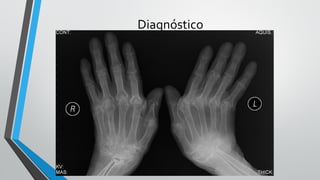

Diagnóstico

Radiologia

•Fases inicias – pode não haver alteração

•Alterações radiológicas

• Erosões justaarticulares

• Osteopenia periarticular

• Redução do espaço articular